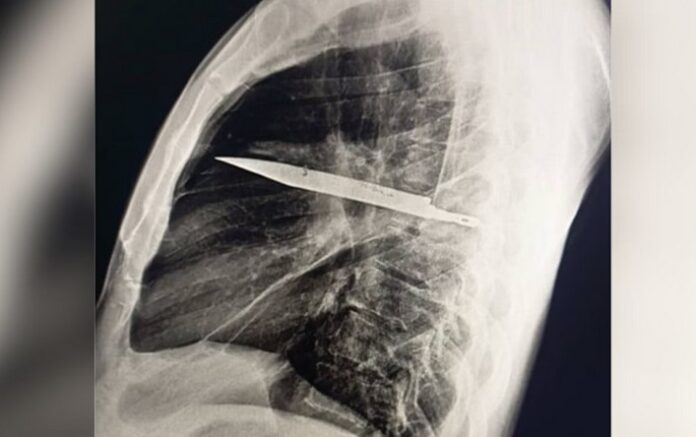

Durante a avaliação recente, exames radiológicos revelaram que a lâmina estava alojada no lado direito do tórax, próxima à escápula, sem atingir órgãos vitais. A secreção com pus foi atribuída à presença do corpo estranho e ao tecido danificado ao redor.